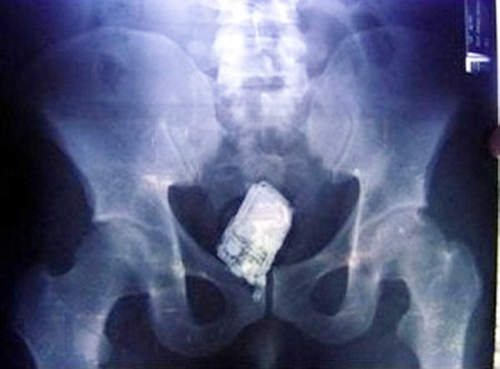

在異物突入X光照的眾多品項裡~要找到能替代電動蘇格蘭的道具無疑就是手機,而這位患者(據說是個律師)在一次洗澡的過程中不小心滑倒整支手機就這麼插了進去~後來動手術取出手機的時候...這支電話還響了三次